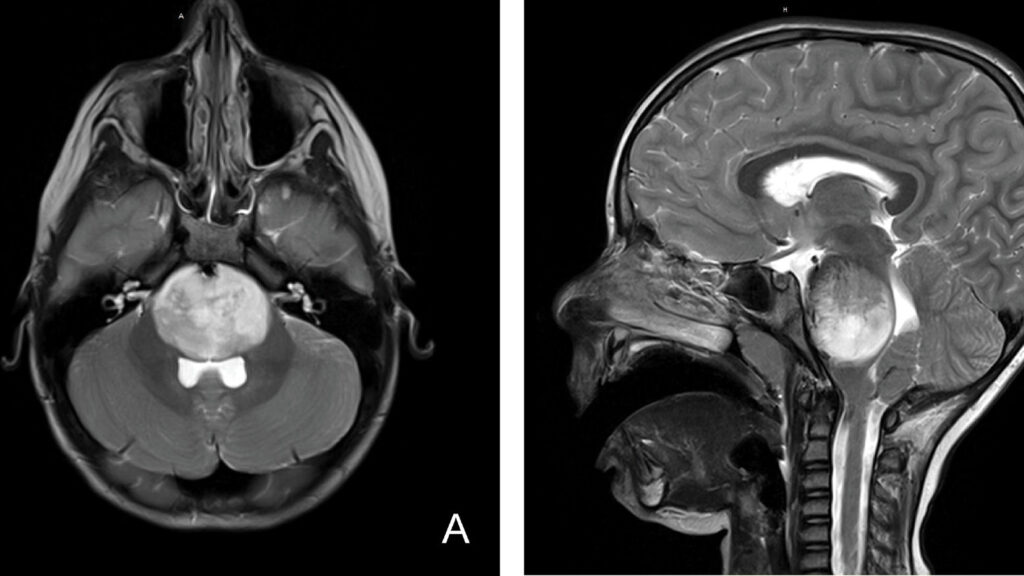

A Guardian feature follows Izzy, a four-year-old with diffuse intrinsic pontine glioma (DIPG), and the families and doctors racing to find experimental treatments as the Trump era’s funding cuts cripple NIH support, shutter the Pediatric Brain Tumor Consortium, and suspend or delay dozens of clinical trials. The result is that progress in DIPG research stalls just as families face a last-hope window, turning access to new therapies into a bureaucratic and political obstacle. In the end, Izzy receives a reprieve when Stanford offers a CAR-T cell trial, a glimmer of hope amid a landscape of lost trials and dwindling resources.